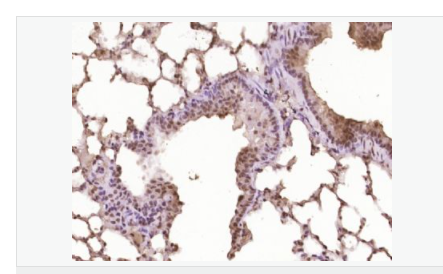

| 產(chǎn)品應(yīng)用 | WB=1:500-2000 ELISA=1:5000-10000 IHC-P=1:100-500 IHC-F=1:100-500 Flow-Cyt=1ug/Test ICC=1:100-500 IF=1:100-500 (石蠟切片需做抗原修復(fù)) not yet tested in other applications. optimal dilutions/concentrations should be determined by the end user. |

| 細(xì)胞定位 | 細(xì)胞核 |

| 產(chǎn)品介紹 | This gene encodes a member of the Notch family. Members of this Type 1 transmembrane protein family share structural characteristics including an extracellular domain consisting of multiple epidermal growth factor-like (EGF) repeats, and an intracellular domain consisting of multiple, different domain types. Notch family members play a role in a variety of developmental processes by controlling cell fate decisions. The Notch signaling network is an evolutionarily conserved intercellular signaling pathway which regulates interactions between physically adjacent cells. In Drosophilia, notch interaction with its cell-bound ligands (delta, serrate) establishes an intercellular signaling pathway that plays a key role in development. Homologues of the notch-ligands have also been identified in human, but precise interactions between these ligands and the human notch homologues remain to be determined. This protein is cleaved in the trans-Golgi network, and presented on the cell surface as a heterodimer. This protein functions as a receptor for membrane bound ligands, and may play multiple roles during development. [provided by RefSeq, Jul 2008]. Function: Notch family members play a role in a variety of developmental processes by controlling cell fate decisions. The Notch signaling network is an evolutionarily conserved intercellular signaling pathway which regulates interactions between physically adjacent cells. The protein is cleaved in the trans-Golgi network, and presented on the cell surface as a heterodimer. This protein functions as a receptor for membrane bound ligands. Once the Notch extracellular domain interacts with a ligand, a protease called TACE (Tumor Necrosis Factor Alpha Converting Enzyme) cleaves the Notch protein just outside the membrane. This releases the extracellular portion of Notch, which continues to interact with the ligand. The ligand plus the Notch extracellular domain is then endocytosed by the ligand expressing cell. After this first cleavage, an enzyme called gamma-secretase cleaves the remaining part of the Notch protein just inside the inner leaflet of the cell membrane. This releases the intracellular portion of the Notch protein, which then moves to the nucleus and causes various genes to be expressed. There are many other proteins involved in the intracellular portion of the Notch signalling cascade. Subunit: Heterodimer of a C-terminal fragment N(TM) and an N-terminal fragment N(EC) which are probably linked by disulfide bonds. Interacts with DNER, DTX1, DTX2 and RBPJ/RBPSUH. Also interacts with MAML1, MAML2 and MAML3 which act as transcriptional coactivators for NOTCH1. The activated membrane-bound form interacts with AAK1 which promotes NOTCH1 stabilization. Forms a trimeric complex with FBXW7 and SGK1. Interacts with HIF1AN. HIF1AN negatively regulates the function of notch intracellular domain (NICD), accelerating myogenic differentiation. Subcellular Location: Cell membrane; Single-pass type I membrane protein. Notch 1 intracellular domain: Nucleus. Note=Following proteolytical processing NICD is translocated to the nucleus. Tissue Specificity: In fetal tissues most abundant in spleen, brain stem and lung. Also present in most adult tissues where it is found mainly in lymphoid tissues. Post-translational modifications: Synthesized in the endoplasmic reticulum as an inactive form which is proteolytically cleaved by a furin-like convertase in the trans-Golgi network before it reaches the plasma membrane to yield an active, ligand-accessible form. Cleavage results in a C-terminal fragment N(TM) and a N-terminal fragment N(EC). Following ligand binding, it is cleaved by TNF-alpha converting enzyme (TACE) to yield a membrane-associated intermediate fragment called notch extracellular truncation (NEXT). Following endocytosis, this fragment is then cleaved by presenilin dependent gamma-secretase to release a notch-derived peptide containing the intracellular domain (NICD) from the membrane (By similarity). Phosphorylated (By similarity). O-glycosylated on the EGF-like domains. Contains both O-linked fucose and O-linked glucose. Ubiquitinated; undergoes 'Lys-29'-linked polyubiquitination catalyzed by ITCH. Monoubiquitination at Lys-1759 is required for activation by gamma-secretase cleavage, it promotes interaction with AAK1, which stabilizes it. Deubiquitination by EIF3F is necessary for nuclear import of activated Notch. Hydroxylated at Asn-1955 by HIF1AN. Hydroxylated at Asn-2022 by HIF1AN (By similarity). Hydroxylation reduces affinity for HI1AN and may thus indirectly modulate negative regulation of NICD. DISEASE: Defects in NOTCH1 are a cause of aortic valve disease 1 (AOVD1) [MIM:109730]. A common defect in the aortic valve in which two rather than three leaflets are present. It is often associated with aortic valve calcification and insufficiency. In extreme cases, the blood flow may be so restricted that the left ventricle fails to grow, resulting in hypoplastic left heart syndrome. Similarity: Belongs to the NOTCH family. Contains 5 ANK repeats. Contains 36 EGF-like domains. Contains 3 LNR (Lin/Notch) repeats. SWISS: P46531 Gene ID: 4851 Database links: Entrez Gene: 4851 Human Entrez Gene: 18128 Mouse Omim: 190198 Human SwissProt: P46531 Human SwissProt: Q01705 Mouse Unigene: 495473 Human nigene: 290610 Mouse Important Note: This product as supplied is intended for research use only, not for use in human, therapeutic or diagnostic applications. |